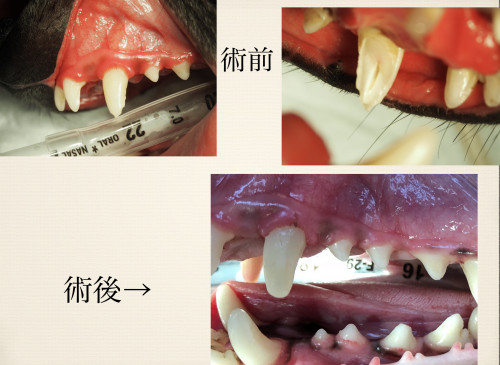

症例写真